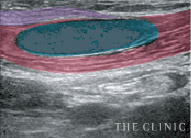

乳腺用エコーでしこりを診断

豊胸手術後のバストを診察する際、触診だけでは正確な情報は得られません。ましてやヒアルロン酸豊胸のしこりは数や大きさ、位置など様々な要素を的確に把握しなければ除去できません。

そのためTHE CLINIC では、全院に導入しているデジタル乳腺用エコー「エラストグラフィ」での検査を必ず実施。的確な診断を元に、治療を行っています。

目視しながら確実にしこり除去

ヒアルロン酸豊胸のしこりの多くは、注射器による処置で除去することが可能です。ただし、それはエコーでしこりを目視しながら、正確にアプローチできた場合のみ。触診だけを頼りに治療を行うクリニックもあるようですが、海外では「暗闇の手術」と呼ばれ、とても危険視されている行為です。

一方、THE CLINIC では、乳腺用エコー「エラストグラフィ」で目視しながら、的確にしこりを除去します。最短ルートでしこりを除去するため、体への負担を最小限に抑えることも可能です。